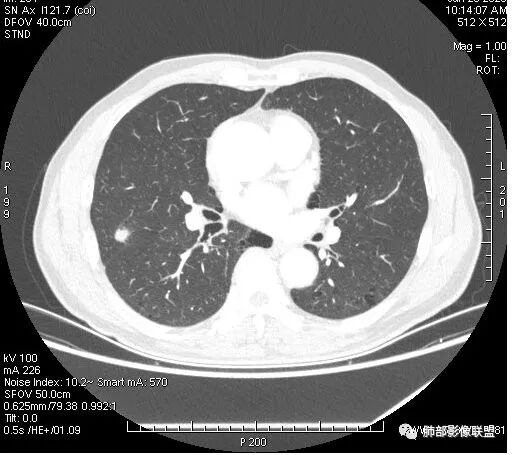

右肺上叶结节,浅分叶膨隆,边缘可见胸膜牵拉及血管集束,不规则厚壁空洞,不均匀强化,血管进入病灶,边缘毛燥,考虑低分化腺癌,鉴别隐球菌。

右肺结节,分叶、长短毛刺,边缘略膨隆,胸膜牵拉,血管进入病灶,收缩力较弱,有血管聚集征,洞壁尚规整,低强化,坏死边缘规整。考虑炎性,隐球,鉴别腺癌。

晨读,右肺上叶结节,边缘膨隆、分叶,部分边缘有平直,可见多发毛刺及胸膜牵拉,牵拉线清秀,收缩力弱,内密度不均,可见片状低密度影及空洞,增强后不均匀强化,血管集束,考虑良性,肉芽肿性结节,鉴别腺癌

晨读:男,67岁,体检发现右肺结节。近圆形,支气管及伴行血管进入结节,进入结节后支气管堵塞,血管走形尚自然,结节内血管边缘凹凸不平。远端边缘见毛刺(软毛刺?)及分叶。见胸膜牵拉。实变中见空洞。整体膨胀感不明显。考虑炎性肉芽肿可能,隐球菌病可能性大。注意鉴别鳞癌、结核。

1.右肺上叶后段类圆形结节影,密度不均,有坏死空洞,坏死比较彻底,内外壁都较清楚。

2.病灶有浅切迹,没有深分叶,毛刺大多细长且柔软。

3.可见棘状突起及胸膜牵拉,但未见胸膜凹陷。

4.病灶轻到中度强化。病灶内血管走行较完好,病灶旁血管局部显示粗大。

5.支气管关系不确定。

6.灶周见小结节影(卫星灶),边界不甚清晰。